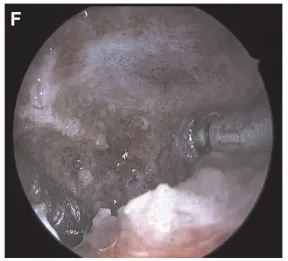

▼在术中神经导航辅助下,探查视神经管并向后追踪探查,以识别并保护右侧颈内动脉(ICA),以识别右侧颈内动脉(ICA)的破裂孔段。进一步钻孔SS下壁,粘膜保持完整并升高。然后暴露斜坡,穿过SS下方。暴露肿瘤上方的正常硬脑膜(图3F)。